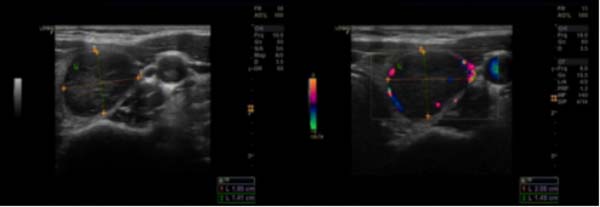

超声所见:甲状腺双叶弥漫性改变,回声不均,内见许多散在低回声区,左叶中部见一个实性低回声区,大小约28×14mm,形态规则,边界清,内部回声不均匀,CDFI:其周边及内部见较丰富血流信号,TI-RADS-3级。

甲状腺透明变梁状肿瘤(hyalinizing trabecular tumor,HTT)是一种向甲状腺滤泡上皮细胞分化的肿瘤。Carney等于1987年报道了11例组织形态学特征不寻常的甲状腺滤泡性肿瘤,并命名为“玻璃样变梁状腺瘤” 。该肿瘤镜下主要以小梁状结构为特征,小梁间有较显著的透明变基底膜样物质沉积,核的特征与甲状腺乳头状癌重叠,并可能与甲状腺髓样癌及副节瘤等肿瘤混淆。HTT临床发病率低,Lee等报道HTT仅占甲状腺结节切除病例的0.2%(10/5111)。该肿瘤女性发病率高于男性,多见于中年女性。临床通常无明显症状,常因体检触诊发现甲状腺结节或影像学检查偶然发现,彩色超声多普勒常表现为甲状腺单发的实性低回声结节,边界清楚,类似于滤泡性肿瘤,结节周边及内部常见血流信号,钙化罕见。